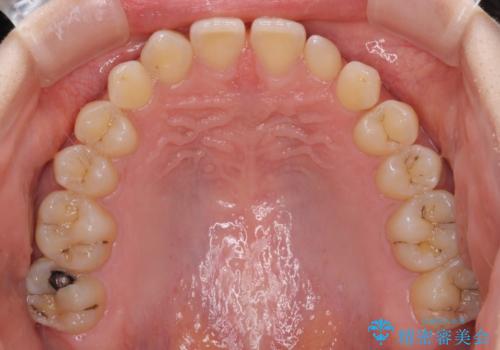

- 前歯の奇形や欠損、乳歯残存などによる審美障害を気にして来院された患者様です。

正中の隙間は矯正治療により閉じ、左右の4歯はオールセラミッククラウンにて補綴することとしました。